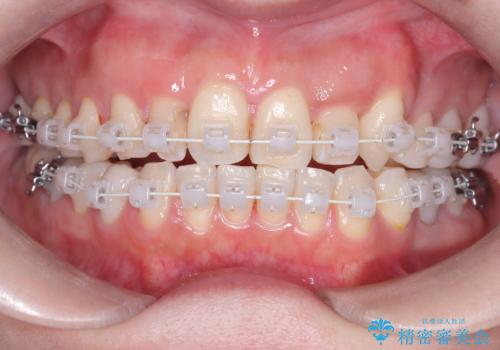

- 40代の患者様で、左上の**八重歯(犬歯の突出)**をずっと気にされていたものの、年齢的な不安から治療を迷われていたとのことでした。精密な検査の結果、左上の歯列に八重歯を収めるための十分なスペースがないことが判明。

40代は歯周組織の健康維持も重要なため、無理な拡大を避け、左上4番(第一小臼歯)を抜歯して確実にスペースを確保する計画を立てました。装置には、歯を三次元的にしっかりとコントロールでき、確実な移動が見込めるワイヤー矯正を選択。八重歯を正しい位置へ誘導し、健康的で美しい口元を目指しました。

まず、計画通り左上4番を抜歯し、そのスペースを利用して八重歯を徐々に正しい位置へと移動させました。ワイヤー矯正特有の「歯を細かく、確実に動かす力」を最大限に活用し、歯根の向きまで丁寧に調整。